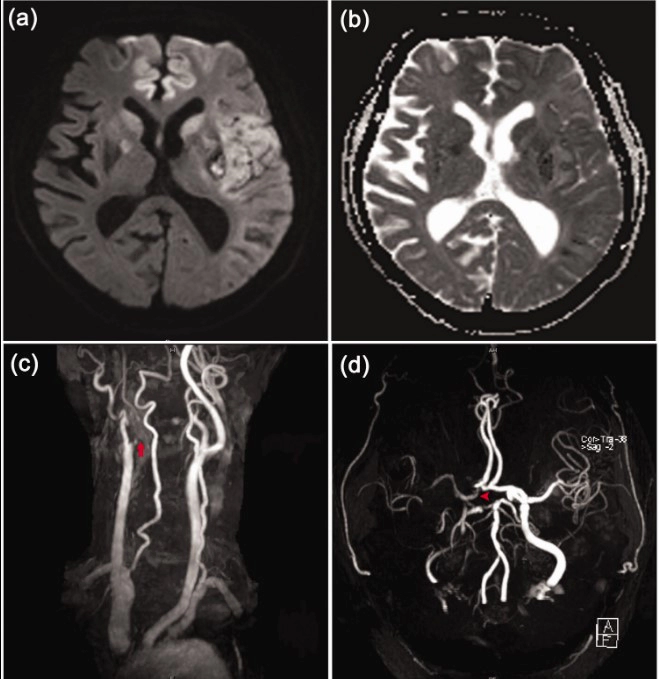

뇌경색, 뇌의 혈관이 막혀 뇌세포가 손상되는 질환은 대부분의 경우 예측이 어렵고, 일단 일어나면 빠르고 적절한 치료 없이는 회복이 어려울 수 있습니다. 그러나 알게 모르게 몸이 우리에게 다양한 신호를 보내어 이를 미리 알아챌 수 있게 해줍니다. 이에 뇌경색의 초기 증상 10가지에 대해 알아보고 뇌경색의 치료 방법과 이에 따른 후유증에 대해서도 자세히 살펴보겠습니다.

뇌경색은 뇌혈관 혈류가 차단되거나 줄어들어 뇌세포가 손상되는 상태를 말합니다. 뇌경색의 초기증상을 파악하는 것은 긴급한 치료가 필요한 상황에서 귀중한 시간을 절약하는 데 매우 중요합니다. 이는 뇌세포가 손상되면 그 부분의 기능을 상실하거나 약화시키는 경향이 있기 때문입니다.